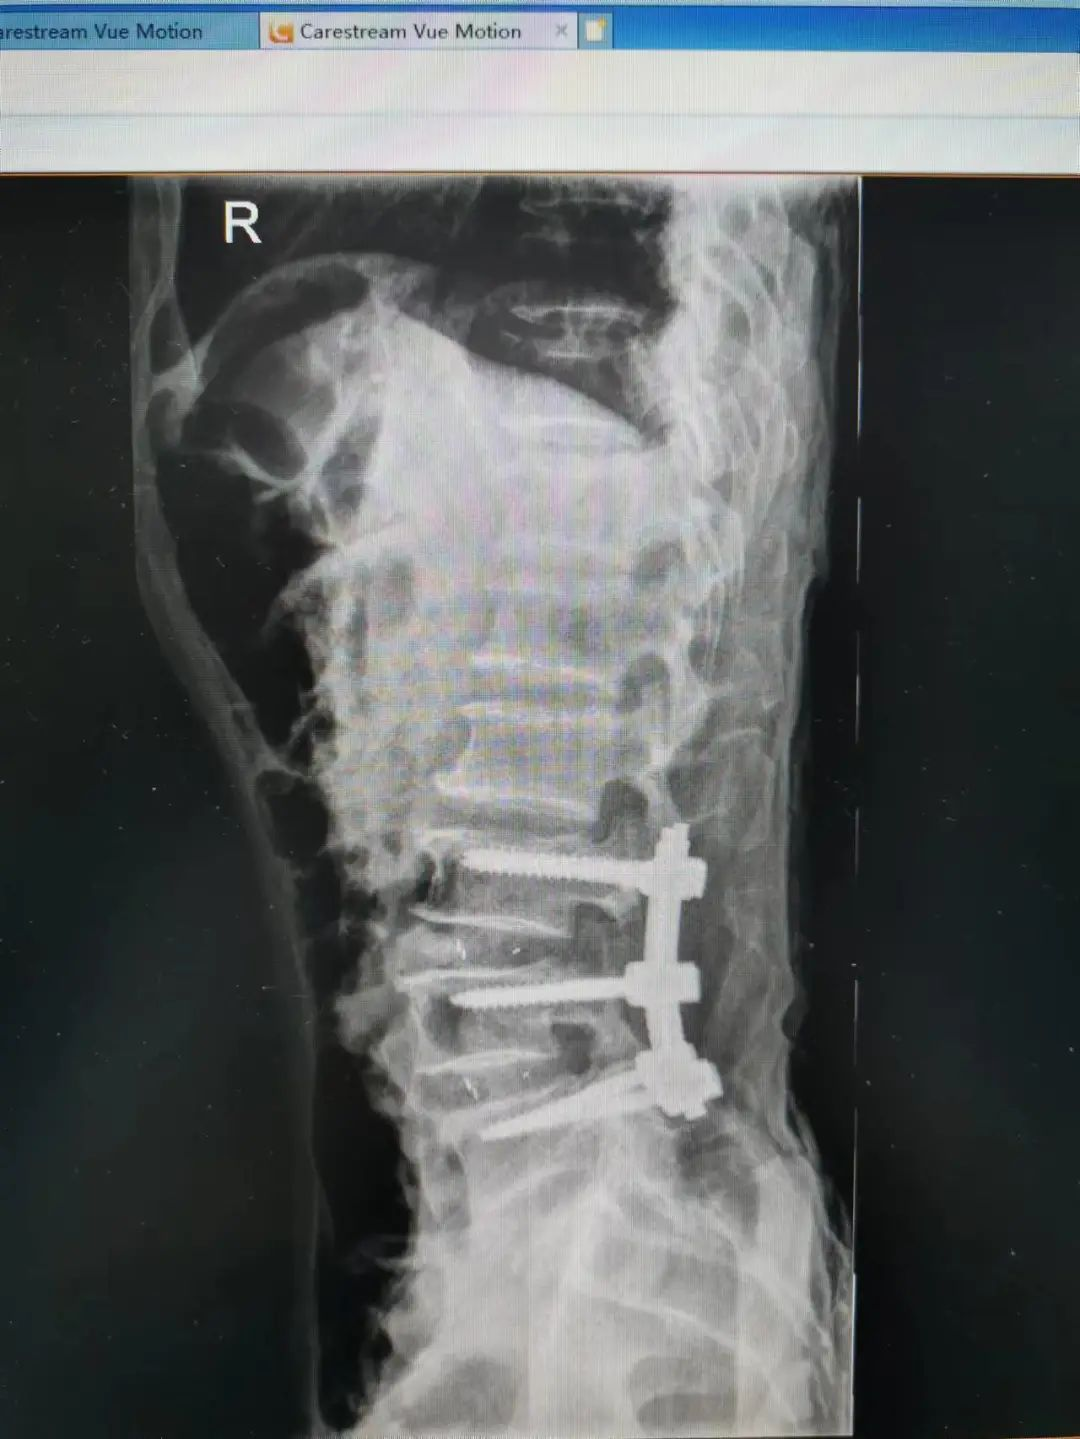

楊先生腰椎管狹窄癥拍片

由于楊先生的病情嚴(yán)重,需住院治療。楊先生入院后,瀘州市中醫(yī)醫(yī)院骨傷二科科主任楊陳一制定了手術(shù)計(jì)劃,決定脊髓型頸椎病的手術(shù)從前路切開減壓,頸3/4 、頸4/5、 頸5/6、 頸6/7椎間盤切除,椎間融合,鋼板內(nèi)固定術(shù)手術(shù),而腰椎管狹窄癥經(jīng)后路切開減壓,腰3/4、腰4/5椎同盤動(dòng)除,椎間融合、釘棒系統(tǒng)內(nèi)固定術(shù)。

楊先生術(shù)后拍片